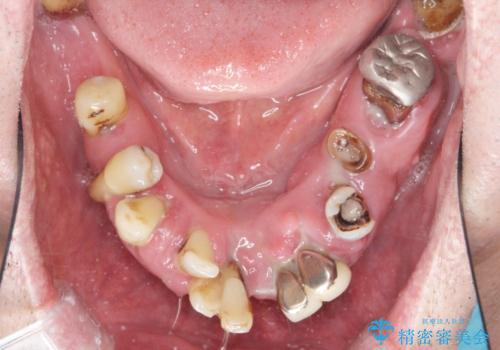

- 見た目を治したい。全体的に治したいとの事で来院。

保存できる歯がなかったので全て抜歯をし、インプラントを埋入し、磁性アタッチメントを用いたインプラントオーバーデンチャーで治療を行いました。